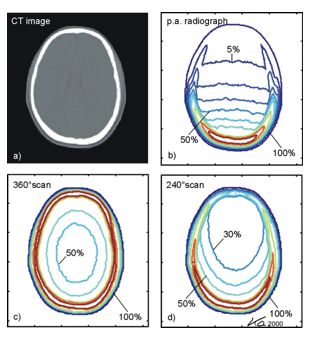

受检者剂量

这一参数必须给予充分地重视。因为诊断工具对病人必须是安全的。设计者必须在病人的剂量与改进分辨力或改进鉴别小密度差别的能力这两方面进行折中考虑。

影响CT剂量的参数有:X射线管电压(kVp)、X射线管电、扫描时间、过滤、射野大小、 病人在射野中取向和位置、源的准直 、层厚和层距、扫描层数目等

单次扫描剂量可采用剂量指数(CTDI)来描述:

CTDI是长度剂量乘积除以断层厚度的商。长度剂量乘积是地区性剂量对整个剂量剖面在轴上的积分。

美国的FDA(美国食品药品监督管理局)对剂量指数(CTDI)作如下定义:

我国的国家标准对剂量指数(CTDI)作如下定义:

沿着垂直于体层平面方向上的剂量分布除以X射线管在360 °的单次旋转时产生的体层切片的数目N与标称切片厚度T的乘积从-50mm到+50mm的积分。